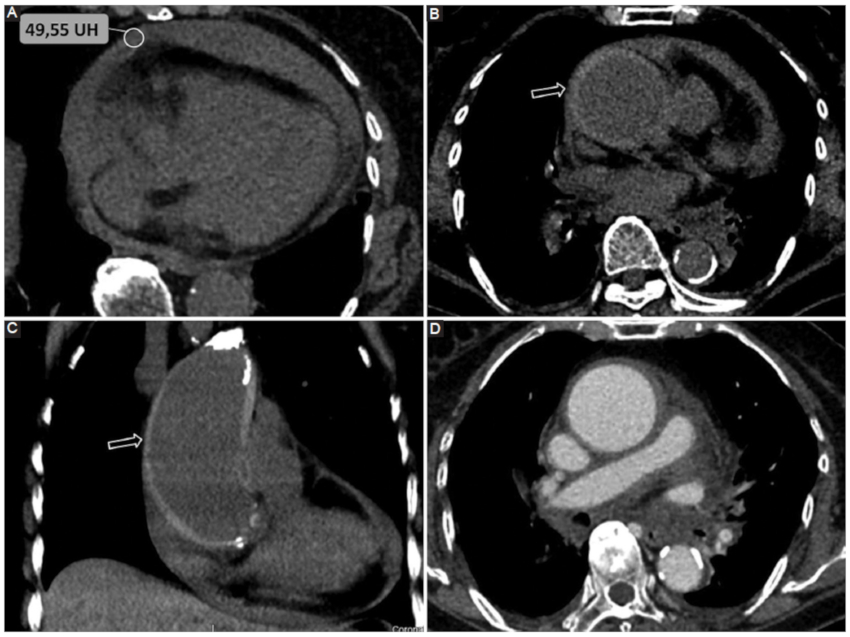

Por su parte, el análisis de la densidad del DP resulta una herramienta complementaria útil y accesible. Se ha estudiado la composición del DP por medio de la medición de densidades tomográficas y su correlación con los datos del análisis bioquímico. En este sentido, una densidad promedio similar a la del líquido es indicativa de trasudado, mientras que valores mayores a 20 UH se vinculan con exudados y mayores a 50 UH con contenido hemático con alta especificidad (Fig. 1) (3,7.

Pericarditis aguda

Se define como un síndrome pericárdico de tipo inflamatorio que puede darse con o sin DP acompañante («pericarditis seca»)6.

En la mayor parte de los casos se trata en un cuadro idiopático (presumiblemente asociado a infecciones virales), aunque puede manifestarse en el contexto de enfermedades sistémicas como tuberculosis, enfermedades autoinmunes, como hallazgo o complicación posquirúrgica, o asociado a compromiso miocárdico (Figs. 5, 6 y 7) (5,6.

Si bien tradicionalmente se la describe en su forma aguda, también puede darse en curso subagudo o crónico. Los síntomas clásicos de presentación incluyen: dolor torácico agudo, de tipo pleurítico que cambia de intensidad con la posición y signos de fricción pericárdica. Los cambios clásicos en el electrocardiograma (ECG) y la elevación de marcadores serológicos de inflamación apoyan el diagnóstico6.

Entre los signos clásicos de pericarditis aguda por TCMC se describen:

DP: particularmente del tipo exudado, aunque en una minoría de casos puede ser trasudado10.

Engrosamiento del pericardio. Habitualmente las hojas del pericardio miden entre 1,3 y 2,5 mm. Un aumento mayor a 4 mm presenta una alta especificidad para esta patología10.

Realce pericárdico tras la inyección de contraste endovenoso (alta especificidad) (10.

Cabe mencionar que Hammer et al. (10, en su serie de 46 pacientes con diagnóstico de pericarditis aguda, encontraron que el engrosamiento y realce pericárdico valorado por TCMC presenta una sensibilidad del 54-59% y una especificidad del 91-96%10.